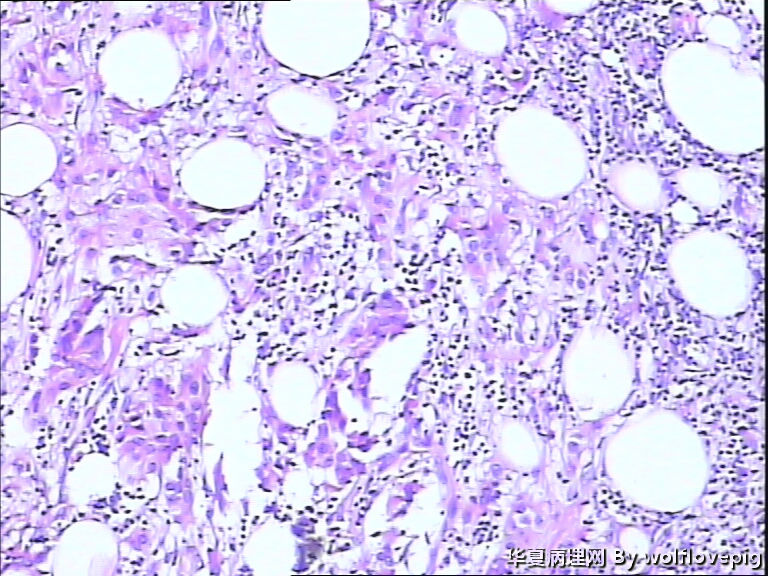

女,60y,发现右乳包块6+月。

灰白不整形组织一块:3*2*1.5cm,切面有一灰白区域,边界欠清,质韧。

标签:乳腺浸润性癌

浸润性癌。

浸润性导管癌,最好标记肌上皮。

浸润性导管癌

浸润性导管癌,分化差,除外混合癌(导管癌+小叶癌),免疫组化证实。(本例图像很多,局部炎症反应重,瘤细胞还成合体样无腺管形成似髓样癌,局部似炎性乳癌,局部似小叶癌,呵呵)